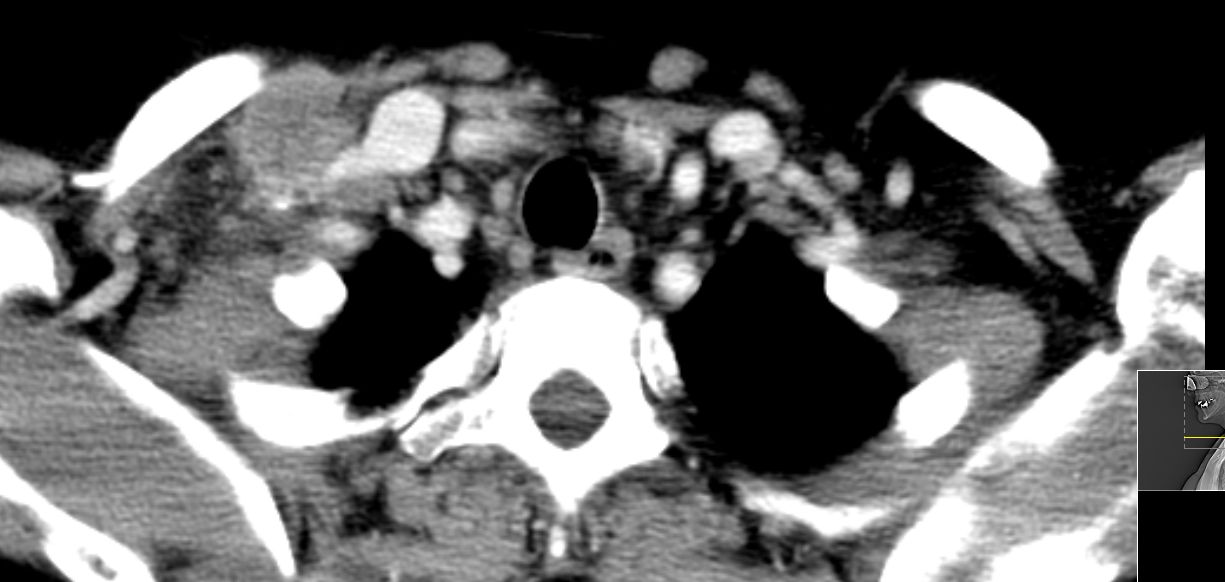

supraclaviculäre Lymphknoten |

52-jährige Frau, bei der vor einem Jahr ein 15 mm großes invasiv-duktales Mammakarzinom rechts o/iq nach 3 Wochen Letrezol (Adapt-Studie) operiert wurde. Postoperativ ypT1c, ypN0 (0/2 sn), cM0, L1 V0 R0, G2, ER: 6/12, PR: 0/12, HER-2/neu: negativ, Ki-67: 30%, Oncotype DX Recurrence Score 40. CHT: 8 x nabPaclitaxel -> 4 x EC. Dann Bestrahlung der Brust. AHT mit Letrozol. Jetzt palpable Lymphknotenmetastasen supraklavikulär rechts. CT: Die teilweise rechts retroklavikulär hinter der rechten medialen Klavikula und supraklavikulär gelegenen Lymphknotenmetastase hat eine Größe von maximal 2,5 cm. Weiter oberhalb und dorsalseitig sind im rechten unteren Halsdreieck dorsal der rechten Vena jugularis externa konfluierende inhomogene Lymphknoten mit Einzelgrößen bis zu 1,5 cm und einer Gesamtpaketausdehnung bis zu 4 cm sichtbar. | ||